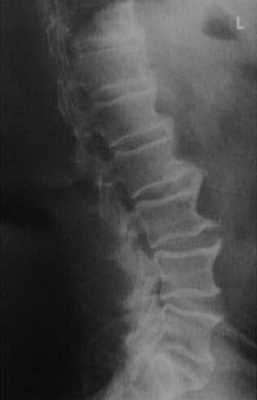

Мужчина 67 лет с диффузным идиопатическим гиперостозом скелета в грудопоясничном сочленении. Рентгенологическое исследование демонстрирует изображение в виде «капель восковой свечи» вследствие мостовидных остеофитов позвонков. Ширина пространства межпозвонкового диска остается относительно нормальной.